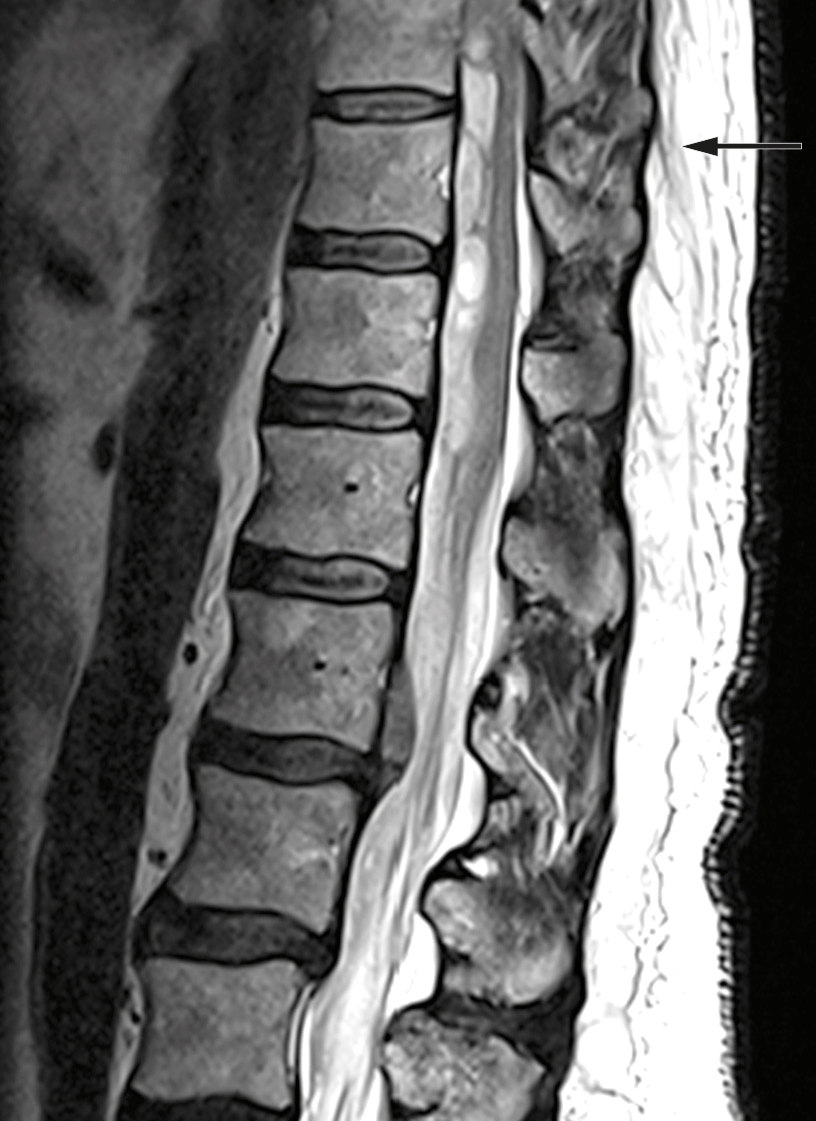

Undersøkelser ved den aktuelle innleggelsen viste blodtrykk 146/68 mm Hg, puls 70 slag/min, Hb 15,4 g/dl (referanseområde 13,4–17,0 g/dl), trombocytter 241 ∙ 109/l (145–390 ∙ 109/l), kreatinin 72 µmol/l (60–105 72 µmol/l) og hurtig-INR 2,6 (innenfor målområdet på 2–3). MR-undersøkelse viste intraspinalt subduralt hematom i nivå Th9–L1 med dislokasjon av ryggmargen og conus medullaris (figur 1). CT-angiografi viste ingen tegn til karmalformasjon eller arteriovenøs fistel. Etter tolkning av haste-MR fikk pasienten fytomenadion (Konakion, 10 mg) og protrombinkomplekskonsentrat (Octaplex, 2 500 IE), dosert etter NevroNELs anbefalinger (4) for å unngå ytterligere blødning.